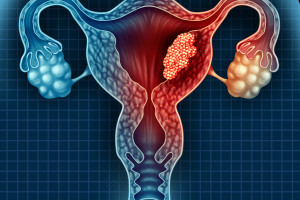

Léčba pokročilého a metastatického endometriálního karcinomu stále zůstává nedořešenou medicínskou výzvou. Věk nemocných a komorbidity, spojené s častou obezitou a diabetem, omezují možnosti agresivní chemoterapie u nádoru samostatně na chemoterapii ne příliš citlivého. Jaké jsou aktuální možnosti terapie?

Autor: MUDr. Vlasta Raušová

Karcinom děložního hrdla je celosvětově čtvrtým nejčastějším nádorovým onemocněním u žen a má za následek více než 300 000 úmrtí na celém světě. Možnosti léčby zahrnují chirurgické zákroky, radioterapii, chemoterapii a cílenou antiangiogenní léčbu. Nádory zachycené v pozdním stadiu mají vysoké riziko recidivy, které se může pohybovat až v desítkách procent. Jaké možnosti přináší imunoterapie?